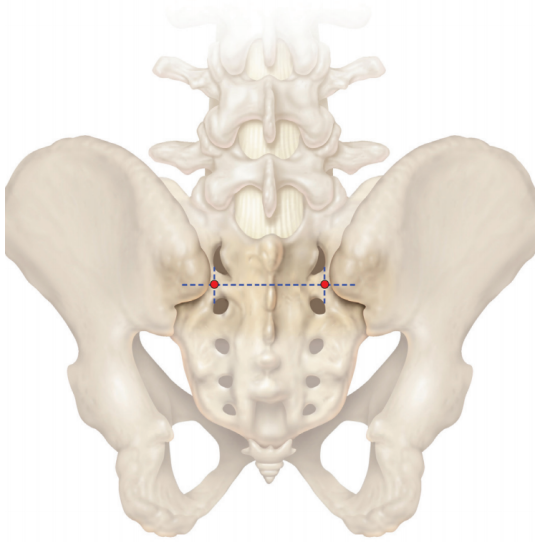

解剖學(xué)上為S1和S2背孔中點(diǎn)的橫向連線,與S1/S2背孔邊緣的縱向連線交點(diǎn)

該點(diǎn)需與S1的椎弓根釘保持對線